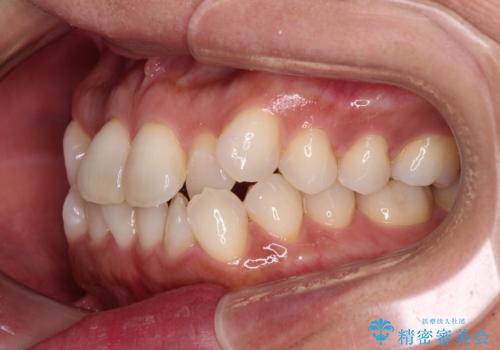

前歯のクロスバイト インビザラインによる矯正治療

- 上下のクロスバイトと前歯のデコボコを気にして来院された患者様です。

インビザラインを用い、IPR(歯と歯の間を削る)と歯列全体を拡大させることで、歯並びを整えていくこととしました。